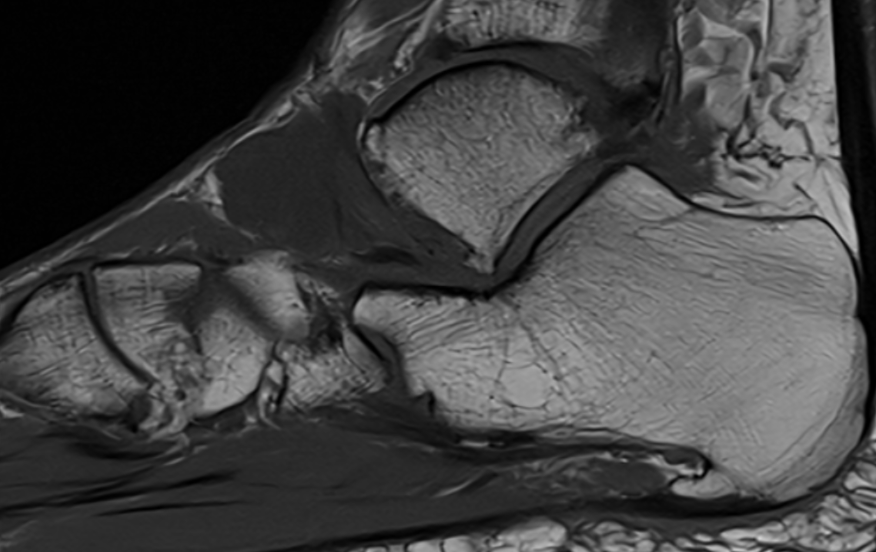

GCT flexor tendon sheath

GCT of tibialis posterior tendon sheath